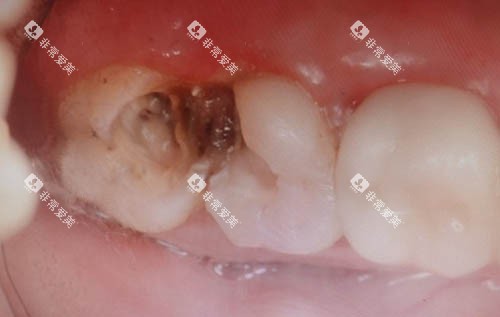

补牙是治疗龋齿的常见方法,能够防止龋齿进一步发展。

在金华地区,补牙的收费价格与补牙材料和龋齿的程度有关。

常见的补牙材料有玻璃材料和树脂材料。

玻璃材料材料价格相对较低,每颗牙齿的补牙费用大约在100 - 300元。

树脂材料的美观度和耐磨性较好,是目前使用较多的补牙材料,其价格也会稍高一些,每颗牙齿的补牙费用在200 - 500元左右。

如果龋齿较为重度,已经接近牙髓,可能需要可靠行垫底处理,这会增加一定的费用,一般在100 - 300元左右。